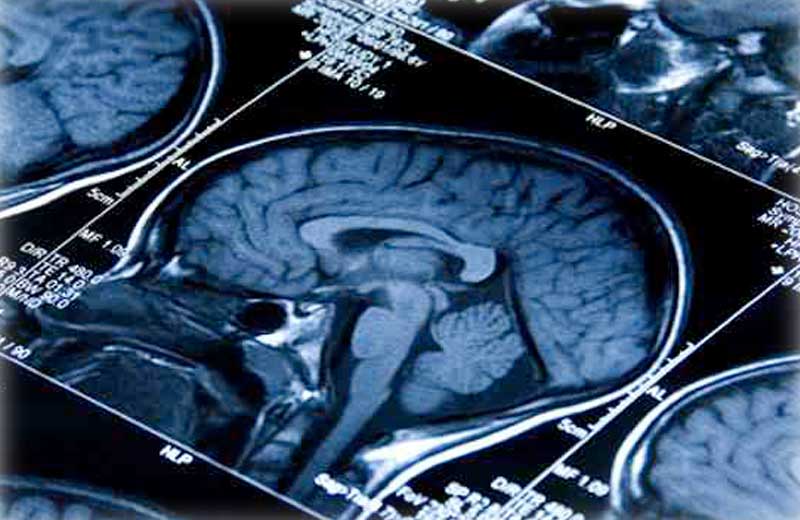

Paciente com câncer no cérebro melhora com droga para malária

Uma nova combinação de medicamentos funcionou bem contra o câncer no cérebro de Lisa Rosendahl, de 26 anos.

“Lisa tinha um glioblastoma agressivo de alto risco e quando começamos esse trabalho, ela já havia tentado de tudo. Para essa população, as taxas de sobrevivência são sombrias”, disse Jean Mulcahy-Levy, pesquisador da Universidade do Colorado Cancer Center.